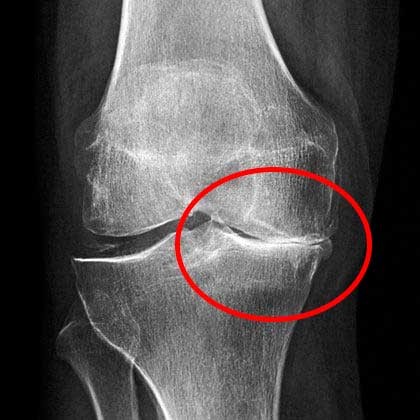

ตอนไปพบหมอครั้งแรก หมอใช้เวลานานมากในการดูภาพเอ็กซ์เรย์ แล้วบอกว่าให้ฉันเลิกทำงานหนักๆได้เลย และห้ามยกของหนักเกิน 2 กิโลกรัม

แน่นอนว่าฉันรับไม่ได้กับเรื่องนี้เลย! แล้วฉันจะทำงานยังไงต่อไป? ฉันรักงานของฉันมาก ไม่ว่ามันจะยากแค่ไหนก็ตาม ในที่สุดฉันตัดสินใจไปปรึกษาหมออีกคน แต่ครั้งนี้ยิ่งทำให้ฉันตกใจไปใหญ่! หมอไม่ได้บอกรายละเอียดของโรคฉันอย่างชัดเจน แต่กลับบอกเลยว่าถ้าไม่ผ่าตัดเข่า ฉันจะกลายเป็นคนพิการ และค่าผ่าตัดแพงมากถึง 1,000 ดอลลาร์! ฉันไม่มีเงินมากขนาดนั้นในตอนนั้น เลยตัดสินใจนัดผ่าตัดไว้หลังจากนั้นอีกหนึ่งเดือนครึ่ง เพื่อที่จะหาเงินมาจ่ายค่าผ่าตัดให้ทัน